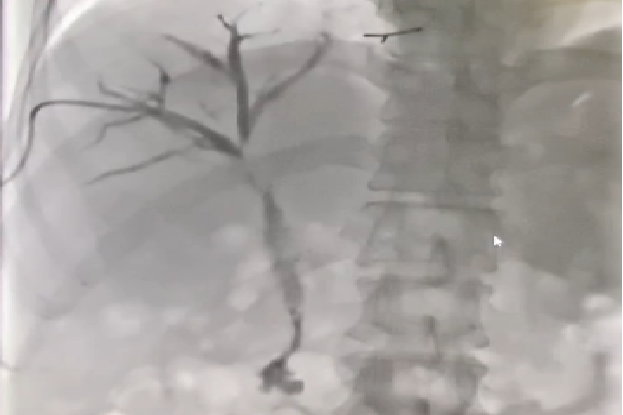

术前:经PTCD管胆道造影

术中:植入两枚8mmX80mm支架

术后4天复查:左胆管造影剂通过原狭窄段良好,顺利流入十二指肠,给予拔除

术后4天复查:右肝部分胆管造影剂排除迟缓,保留右侧胆道引流管,继续外引流,择期复查

术后1月复查:右胆管残留狭窄、造影剂线形通过,考虑患者目前无明显黄疸症状,肿瘤较前有所缓解,为改善生活质量,给予拔除